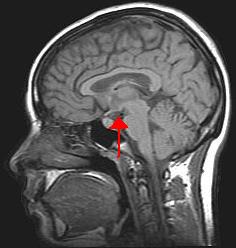

Location of the human hypothalamus | |

Location of the hypothalamus (blue) in relation to the pituitary and to the rest of the brain | |

The hypothalamus (from Ancient Greek ὑπό, "under", and θάλαμος, "chamber") is a portion of the brain that contains a number of small nuclei with a variety of functions. One of the most important functions of the hypothalamus is to link the nervous system to the endocrine system via the pituitary gland. The hypothalamus is located below the thalamus and is part of the limbic system.[1] In the terminology of neuroanatomy, it forms the ventral part of the diencephalon. All vertebrate brains contain a hypothalamus. In humans, it is the size of an almond.